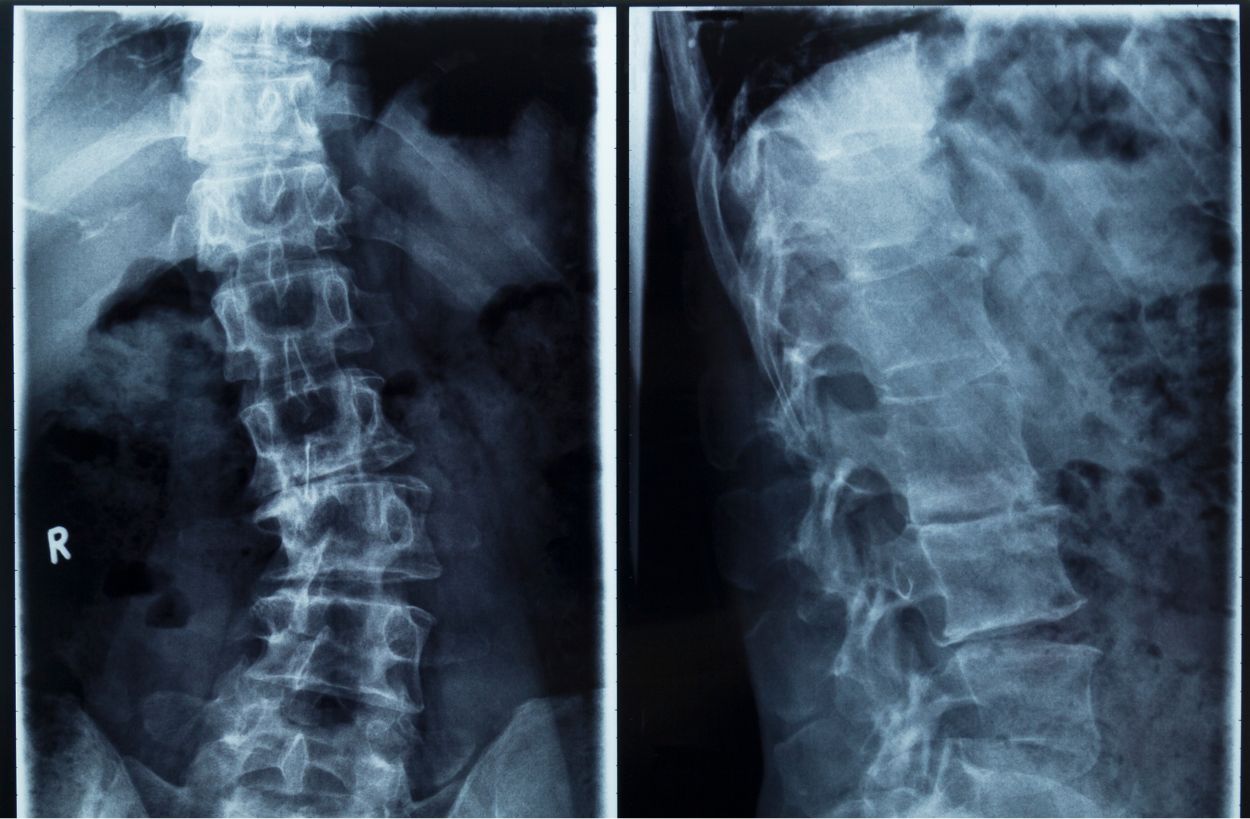

목디스크라는 질환은 디스크(추간판)이라는 척추뼈 사이사이에 위치한 디스크가 변형되면서 경추 신경을 압박하거나 자극하여 목의 통증, 두통, 팔 저림 현상을 일으키는 질환입니다.

목디스크는 허리디스크와 동일한 메커니즘으로 발생하는 척추 신경 질환 중 하나이며, 규칙적인 운동과 올바른 치료가 병행된다면 충분히 개선할 수 있는 질환입니다.

척추 질환

목디스크가 발생하는 가장 흔한 원인은 장기간 잘못된 자세로 인해 척추뼈가 휘거나, 척추 협착증 등으로 인해 디스크가 자극되면서 발생하는 것입니다. 예를 들어 척추 측만증이나, 경추관 협착증 등의 질환이 존재합니다.